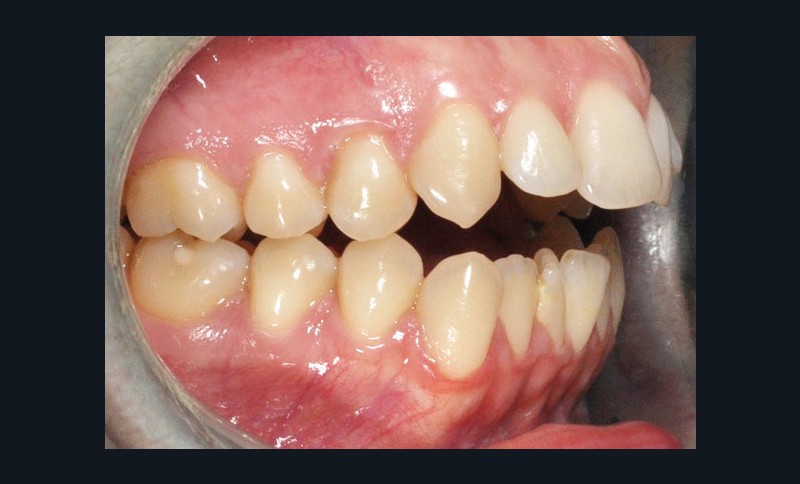

Diagnostic (fig. 1)

Cette patiente de 29 ans consulte pour des raisons principalement fonctionnelles mais également esthétiques. Elle présente :

– une classe II squelettique hyperdivergente

– une endognathie maxillaire

– une classe II division 1 majeure et asymétrique associée à une béance antérieure sévère

– un profil très convexe avec une occlusion labiale difficile et une biprochéilie

– une DDM par défaut modérée, maxillaire et mandibulaire

– des troubles de la posture et de la fonction linguale.